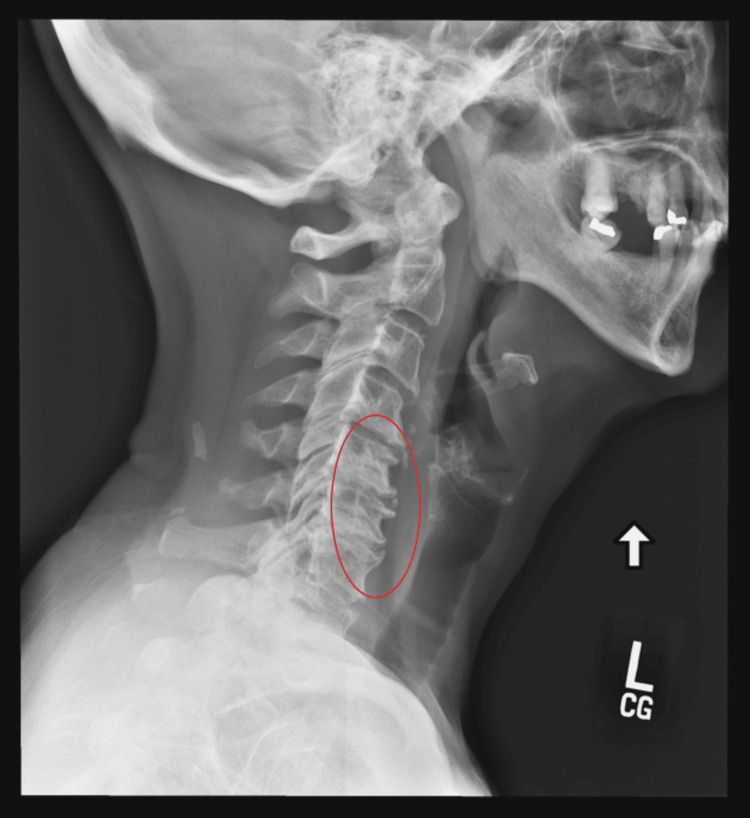

A 72-year-old female presented to her primary care physician with chronic neck and lower back pain and diffuse arthritic pain, secondary to scleroderma and osteoarthritis (OA). She had an extensive past medical history, including hypothyroidism, primary hypertension, hyperlipidemia, migraine, depression (recurrent without suicidality), insomnia, and osteopenia. Prior management with multiple oral medications, such as oxycodone-acetaminophen (10-325 mg) twice daily, oxycodone (20 mg, extended release 12 hours) twice daily, gabapentin (300 mg) up to five times daily, and intermittent cannabidiol ointment (dose not reported), ineffectively treated her pain. She stated that her lower back pain started around the age of 25, with no specific factor causing the onset indicated in her medical record. The patient at the time was healthy and did not have obesity. At times, the severity of the pain was forcing her to crawl around her house or at work due to exacerbations caused by standing and walking. The patient recently reported that her pain had markedly worsened, primarily in her lower back, and her neck pain became more severe and constant. Her BMI was 33.8 kg/m², and her examination was positive for diffuse tenderness in the lumbar area with associated paravertebral spasm. A cervical spine X-ray showed severe interspace narrowing at cervical spine vertebra C5/6 and C6/7 and moderate narrowing at C4/5 and overall cervical spondylosis/degenerative changes of the cervical spine (Figure 1).